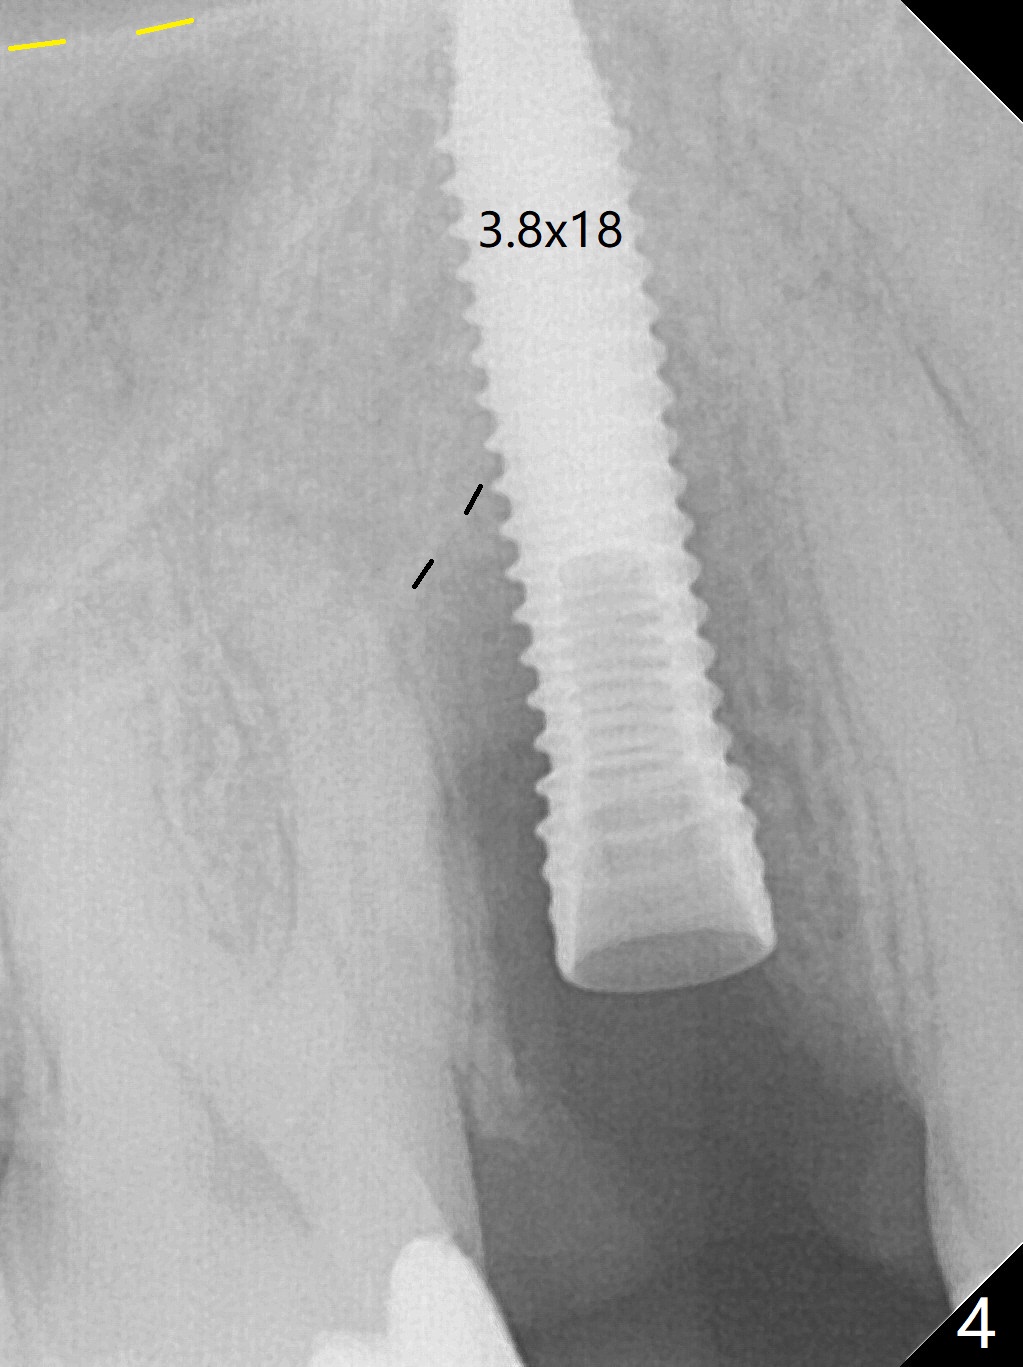

When the tooth #4 with vertical root fracture (Fig.1) is extracted, the buccal plate is found to be lost. The lowest point of the defect is shown as black dashed line in Fig.2 (yellow dashed line: sinus floor). After use of 2.5 mm reamer for 21 mm (buccal gingival level) and 3.0 mm reamer for ~17 mm, a 3.8x15 mm dummy implant is placed with 30 Ncm and 1.85 mm apical space (Fig.3 pink outline). A 3.8x18 mm (definitive) implant is placed with <40 Ncm with the implant plateau apical to the lingual crest (Fig.4,5). The buccal plate defect is repaired by Vanilla Graft (Fig.6 *) before and after insertion of a 4.5x4(3) mm abutment. The buccal plate defect seems to being repaired 4 months postop (Fig.7). Occlusal wear suggests bruxism, which is also associated with the root fracture. Night guard is recommended. The defect repair is close to completion 8 months post cementation (Fig.8). The crown/abutment is found to be loose 1 year 4 months post cementation and retightened without checking whether there is clinical 2nd DO caries of #3 (Fig.9, "sensitive to water pik"). A few days later, DO composite is being removed. It is difficult to determine whether the 2nd DO caries or gap has been removed with the neighboring crown in place. When the crown/abutment is removed and gingival retractions are inserted, there is no decay. The gap is removed. With Toflemire in place, the crown/abutment is reseated and hand tightened; after packable composite, the crown/abutment is removed, there is no more DO gap.

In fact there is a small buccal fistula, which is communicated with the underlying implant threads. Although preop CT shows that the buccal crest is lower than the palatal (3.8x13 mm, Fig.10 P) one, intraop finding of missing buccal plate should dictate a shorter implant (Fig.11) or onlay graft to avoid periimplantitis. Regeneration of the bone plate is limited. Later the fistula disappears with formation of a concavity (Fig.13). There is no symptom. Is bone graft necessary with a remote incision? 3-D images of CT taken 1 year 5 months post cementation show possible mesiobuccal and distopalatal bony defects (Fig.13-16). It is possible that bone graft was placed enough palatal (Fig.16). DO composite at #3 is redo satisfactorily (Fig.17 *).